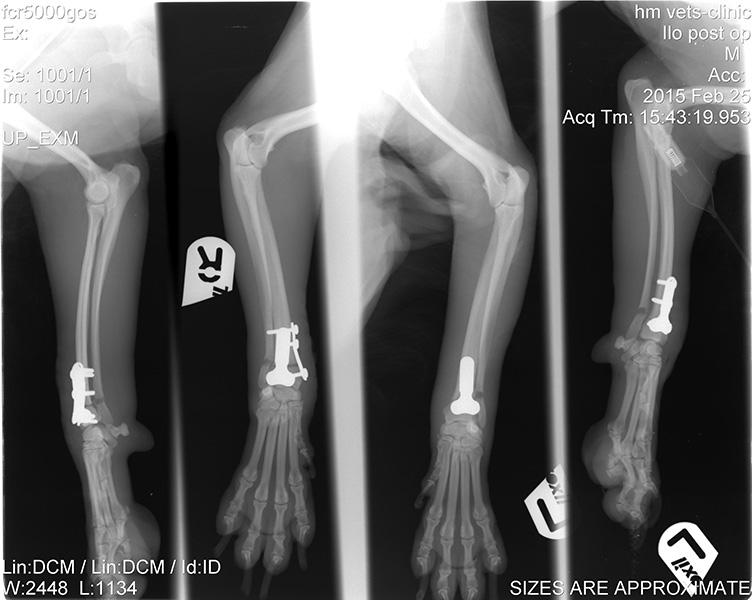

Ορθοπεδική

Ορθοπεδική

Το κτηνιατρείο hm vets αναλαμβάνει ψηφιακή ακτινογραφία, έλεγχο δυσπλασίας ισχίου, ορθοπεδική-νευροχειρουργική, χειρουργική μαλακών μορίων, οφθαλμολογία, εσωτερική παθολογία και εργαστηριακές εξετάσεις (αίματος, βιοχημικές, ανοσολογικές, ορμονολογικες, μοριακές και ιστοπαθολογικές).

Το κτηνιατρείο hm vets αναλαμβάνει ψηφιακή ακτινογραφία, έλεγχο δυσπλασίας ισχίου, ορθοπεδική-νευροχειρουργική, χειρουργική μαλακών μορίων, οφθαλμολογία, εσωτερική παθολογία και εργαστηριακές εξετάσεις (αίματος, βιοχημικές, ανοσολογικές, ορμονολογικες, μοριακές και ιστοπαθολογικές).